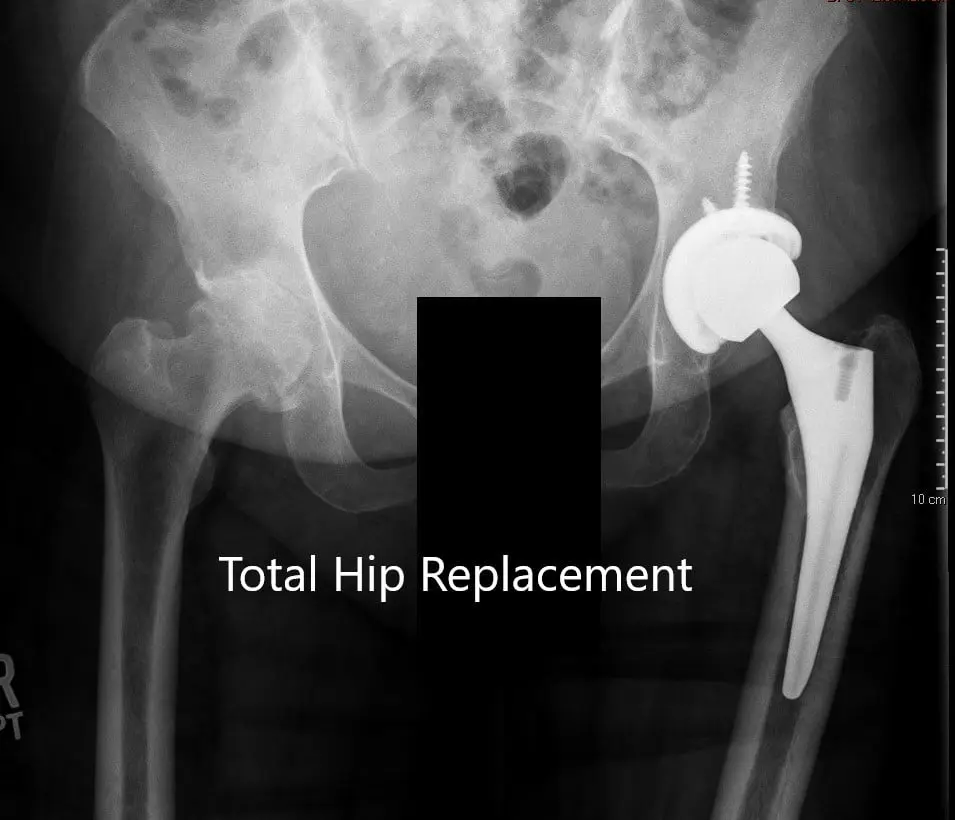

Imaging studies revealed bilateral hip osteoarthritis which was severe in the left hip with dysplasia of the acetabulum. In view of lifestyle limiting hip pain, he was advised left total hip replacement. Risks, benefits, and alternatives were discussed with the patient at length. The patient agreed with the plan.

Preoperative X-ray of the left hip showing AP and lateral views.

Postoperative X-ray showing the AP view of the pelvis and lateral view of the left hip.